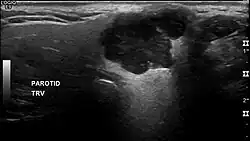

Die Ausdehnung des Befundes kann mittels bildgebender Verfahren (Magnetresonanztomographie, Computertomographie oder Sonographie) ermittelt werden. Eine definitive Diagnose wird vom Pathologen durch histologische Untersuchung des Operationspräparates oder manchmal auch bereits anhand von bei einer präoperativ durchgeführten Feinnadelpunktion gewonnenem Zellmaterial gestellt.[1]